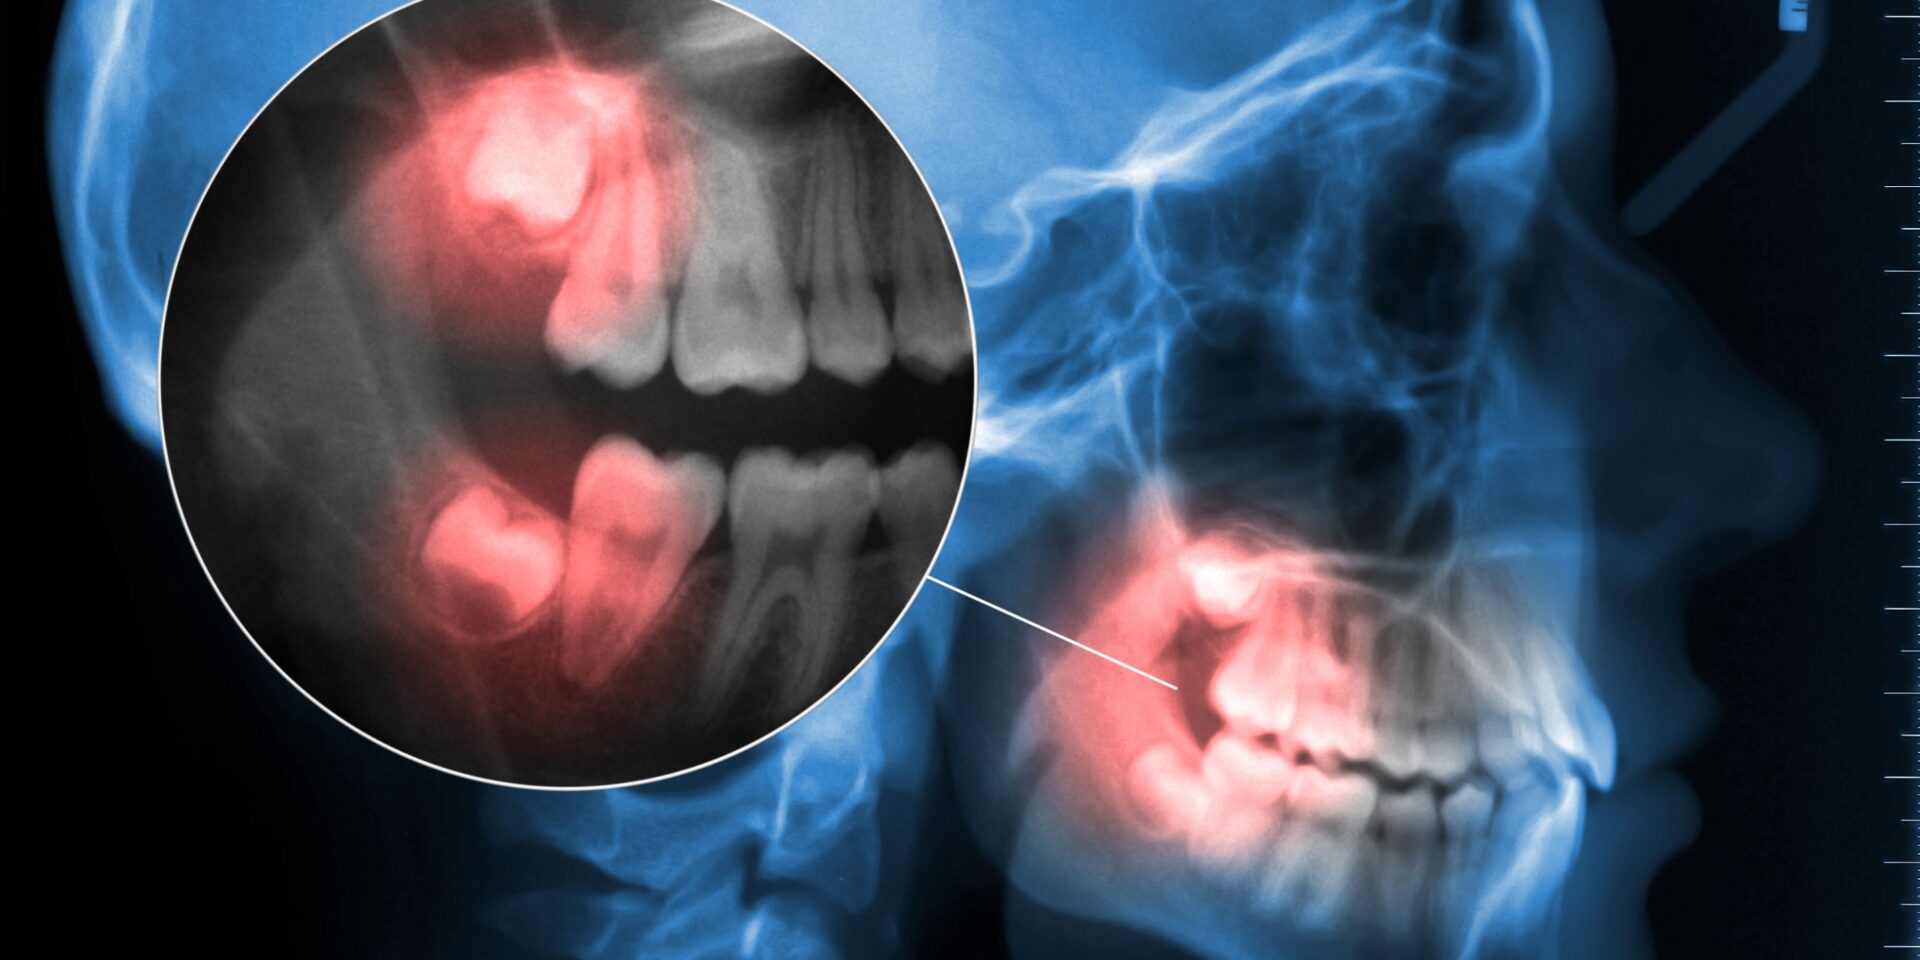

Estas 12 piezas entre arriba y abajo de la boca, no suelen completarse hasta los 18 o 20 años con la llegada de los terceros molares o muelas del juicio, aunque en algunas personas no se desarrollan o se recomienda extraerlos por falta de espacio. La función de los molares es la masticación final.